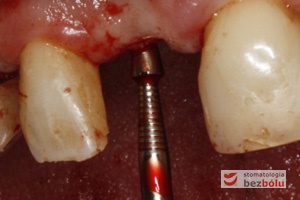

Mapowanie kości - diagnostyka grubości błony śluzowej przy użyciu instrumentu endodontycznego

Mapowanie kości – diagnostyka grubości błony śluzowej przy użyciu instrumentu endodontycznego